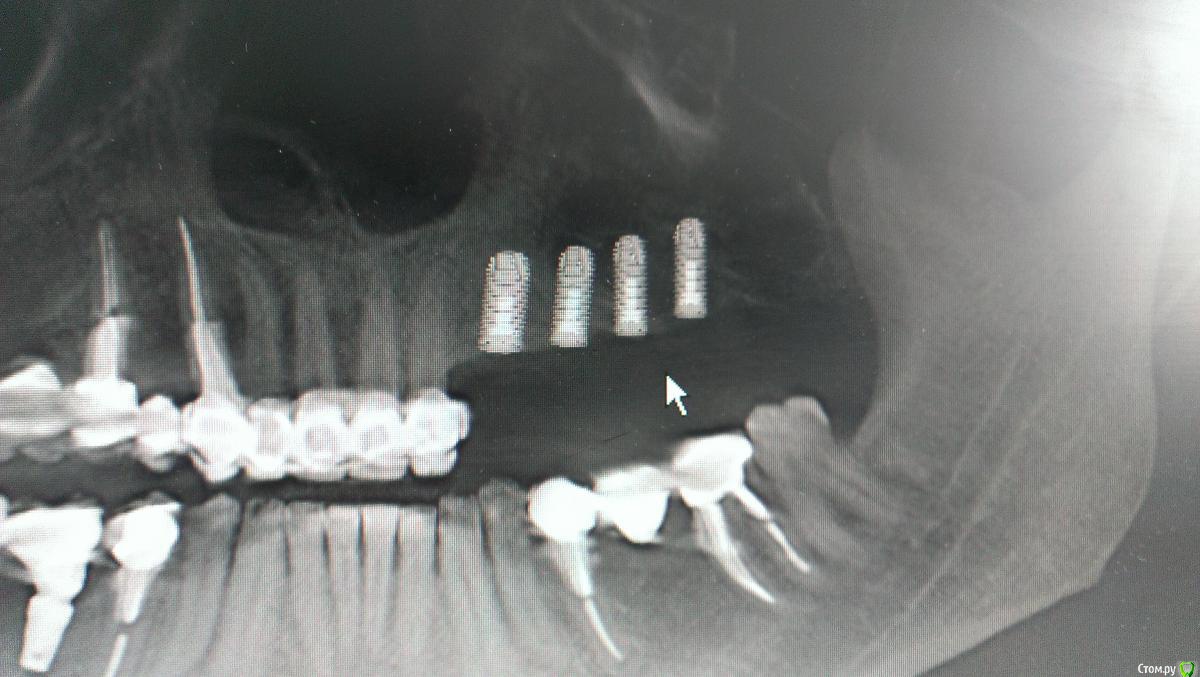

AlexFox Опубликовано 13 июля, 2016 Поделиться Опубликовано 13 июля, 2016 Доброго времени суток,коллеги.Огромная просьба к имплантологам поделиться своим мнением по-поводу клинического случая.Пациенту 45 лет,жалобы на отсутствие жевательной группы зубов во втором сегменте.Для постановки имплантов требуется синуслифтинг.Меня настораживает малый объем имеющейся костной ткани при большом объеме поднятия дна.Плюс слизистой на кт я вообще не вижу.Хотелось бы узнать ваше мнение об этом. Ссылка на комментарий

BugDan Опубликовано 14 июля, 2016 Поделиться Опубликовано 14 июля, 2016 (изменено) Я бы сделал синус с ауто-ксено 1:1 по причине чистой кортикалки в области моляров.Ставить ли импланты сразу или нет зависит от макродизайна имплантатов котрыми вы планируете пользоваться и опыта в первую очередь.На картинках планирования 23 стоит далековато от 22 , винт 5 стоит чуть медиальнее чем надо, а 6 сильно медиальнее чем нужно. Для страховки просмотрите латеральную стенку синуса на предмет артерии. Изменено 14 июля, 2016 пользователем BugDan Ссылка на комментарий

Astronaft Опубликовано 14 июля, 2016 Поделиться Опубликовано 14 июля, 2016 23 занчительно мезиальнее надо.Я бы ограничился 3 винтами задесь, поставив 25 под углом, что бы вышел на 26. 1 Ссылка на комментарий

AlexFox Опубликовано 14 июля, 2016 Автор Поделиться Опубликовано 14 июля, 2016 Спасибо,коллеги.На основании ваших замечаний изменил постановку имплантов.Выложил фото,буду рад вашим коментариям Ссылка на комментарий